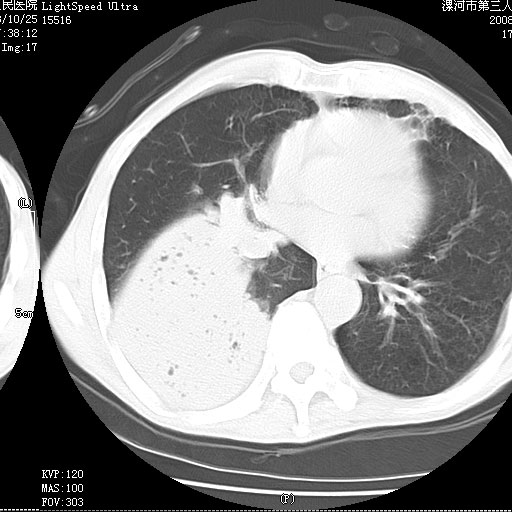

按肺叶分布,考虑肺不张

叶间裂前移,能考虑肺不张和肺栓塞吗?为什么不增强?大叶肺炎不能考虑吗?

右下肺实变,内有弥漫分面小气泡而无支气管征,叶间裂前移,呈臌大之形,而无收缩之状,兼纵隔稍左行移,故。不支持不张,倒支持大叶肺叶,如楼上所说,小气泡不象残留之肺,不可以考虑产气菌感染吗。

坠积性肺炎合并右下肺膨胀不全

考虑为右肺下叶支气管痰栓形成并阻塞性肺不张及肺炎。

考虑为右肺下叶支气管痰栓形成并阻塞性肺不张及肺炎。支持

考虑右肺下叶脓肿,右肺下叶支气管痰栓。